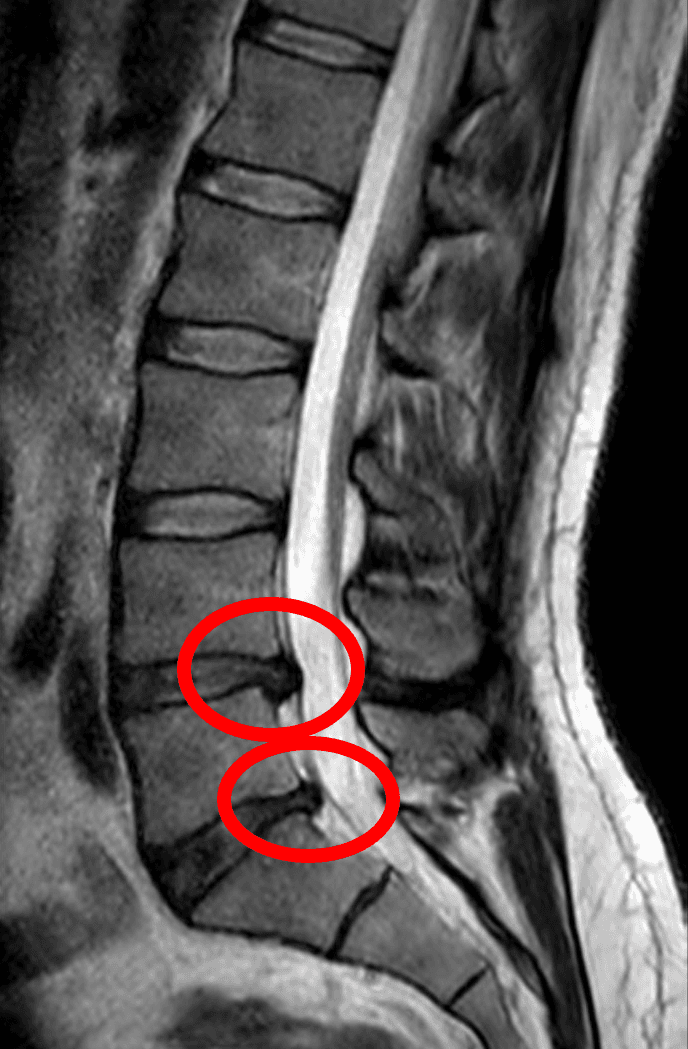

Une est une lésion atteignant le rachis et caractérisée par le déplacement d'une partie d'un disque intervertébral hors des limites de sa situation normale. En principe, cette hernie est la conséquence d'une ouverture dans l'anneau fibreux laissant passer une partie du noyau pulpeux, plus mou, à l'extérieur de cet anneau. La hernie discale est habituellement en rapport avec une lésion dégénérative du disque liée à l'âge, pouvant être favorisée par un traumatisme ou des efforts répétés. Le plus souvent la hernie est localisée au niveau postérolatéral, ce qui est favorisé par la présence du ligament longitudinal postérieur dans le canal vertébral. En principe, la douleur résulte de la compression d'une racine d'un nerf spinal, l'exemple le plus fréquent étant la lombosciatique résultant d'une hernie discale de niveau lombaire. Les symptômes en rapport avec la hernie discale sont le plus souvent d'évolution favorable en quelques semaines avec un traitement médical symptomatique. Rarement, un traitement chirurgical est requis. vignette|upright=2|Schéma d'une coupe transversale du rachis cervical passant au niveau d'un disque ; à gauche : aspect normal ; à droite : hernie discale postérolatérale gauche. Les disques intervertébraux sont situés, comme leur nom l'indique, entre deux vertèbres sus - et sous-jacentes, au niveau du rachis cervical, thoracique et lombaire. Il n'y a cependant pas de disque entre les vertèbres C1 et C2 qui s'articulent différemment. Il existe également un disque entre la cinquième vertèbre lombaire et le sacrum. On distingue au total 23 disques intervertébraux, nommés d'après les vertèbres adjacentes. On décrit une hernie selon sa direction. Ainsi, dans le plan axial, on décrit les hernies médianes, postérolatérales ou paramédianes, foraminales et extraforaminales. Dans le plan sagittal, on décrit les hernies ascendantes et descendantes. On distingue les hernies exclues (vis-à-vis du ligament longitudinal postérieur), saillantes (par définition) ou non (forme incomplète de hernie discale).